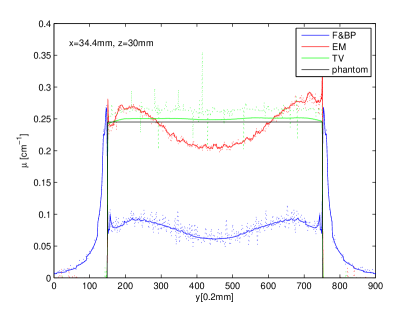

In Figs. 3, and 4, we show the image profiles on three different lines through the reconstructed image within the center plane (i.e., mm) of the image. The reconstruction properties discussed above can be observed in these profile results. Clearly, the FBP reconstruction appears most noisy, which is expected because the ramp filtering tends to amplify noise. There is a considerable DC shift for FBP reconstruction, as well as for the EM reconstruction. From the profile across spheres of varying diameters in Fig. 3, it can be observed that that in-plane resolution is maintained in DBT, which is the reason for the clinical usefulness of DBT. The profile in Fig. 4 is on a line through a uniform section of the phantom. Uniformity appears to be best reproduced by the TV reconstruction. In the TV reconstruction, a shift between noiseless and noisy data can be observed.